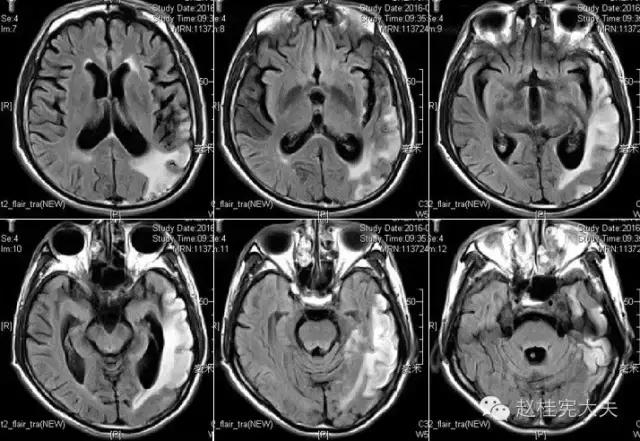

入院前1天的头颅CT:

定位诊断:混合性失语,定位于左侧大脑半球语言中枢(运动和感觉),右侧中枢性面舌瘫,定位于左侧面神经核团以上,右侧上下肢肌力降落,病理征阳性,定位于左侧锥体束。感觉、视野查体无法配合,暂无相应定位考虑。综合考虑,定位于左侧大脑中动脉分布范围。头颅CT:左侧颞叶片状低密度影,左侧大脑中动脉下干支配区,支持临床定位。

定性诊断:结合57岁,男性,急性病程,逐渐加重,进展性右侧肢体无力、混合性失语。头颅CT:左侧颞叶片状低密度影。脑梗死为首先考虑,左侧大脑中动脉支配区,大动脉粥样硬化型。尽管患者本人无高血压、糖尿病等危险因素,但患者母亲有中风、糖尿病史,存在家族中风危险因素,故待完善血生化及血管等卒中危险因素筛查。入院后继续急诊抗血小板、降脂稳定斑块及脑保护治疗。

完善检查,头颅MRI回报:左侧颞顶枕叶急性梗死灶。

患者的磁共振影像不符合脑血管病的血供分布,跨了大脑中动脉和大脑后动脉范围,且病灶偏皮层分布。大脑前、中、后动脉血供分布(横断面)见下图

这不是一个真的“脑卒中”,而是一个“卒中样发作”。